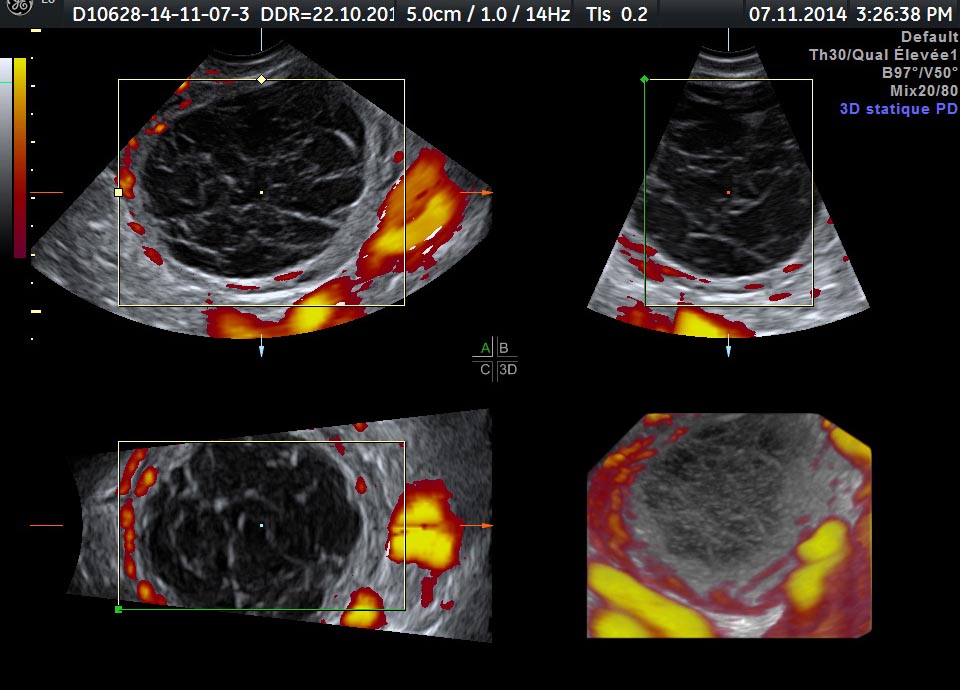

Les HOC peuvent avoir diverses apparences en fonction du stade d'évolution des produits sanguins et du caillot.

• le caillot peut adhérer à la paroi du kyste imitant un nodule, mais ne présente pas de flux sanguin en imagerie Doppler

• il ne devrait pas y avoir de flux sanguin interne

• le débit sanguin circonférentiel dans la paroi du kyste est typique

Les HOC sont généralement détectés par échographie en niveaux de gris, mais ils sont souvent mal diagnostiqués en raison de leur apparence échographique variable. imitant d'autres masses annexielles organiques. La plupart des HOC sont fonctionnels, peu d'entre eux peuvent être néoplasiques mais ils sont universellement bénins  . L'intervention chirurgicale devrait être différée dans la prise en charge des COH, car la plupart d'entre eux disparaissent spontanément avec le suivi. Par conséquent, un diagnostic clinique et échographique sûr doit être tenté pour éviter d'exposer le patient à une intervention chirurgicale inutile  .